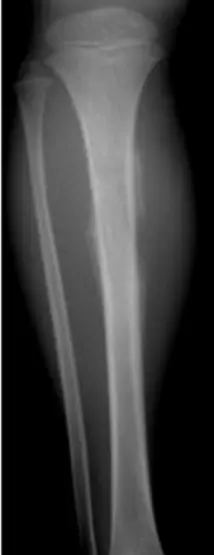

| Compartment Syndrome | Increased pressure within a closed fascial compartment, leading to reduced tissue perfusion, hypoxia, and irreversible muscle and nerve damage. Causes: Fractures (especially tibia/forearm), severe soft tissue trauma, arterial injury, burns, tight casts/dressings, post-ischemic reperfusion swelling, IV fluid extravasation, and bleeding disorders (e.g., hemophilia). High-Risk Notes: Pain may be absent in altered consciousness, children (monitor analgesia response), polytrauma, sedated/epidural cases, or concomitant nerve damage. Open fractures do not always decompress pressure. Gross/Clinical: -tense, shiny leg swelling with blisters in compartment syndrome.Imaging: - Intraoperative fasciotomy | History/Symptoms: Pain out of proportion to the injury (e.g., a “bursting” sensation), which is not relieved by analgesia. Clinical Features (The 5 P’s): - Pain with passive stretch (early, key sign; e.g., ankle dorsiflexion for leg, wrist for forearm). - Paresthesia (early). - Palpable tense swelling (shiny skin, blisters: clear=mild, serosanguinous=severe, bloody=worst; dusky/pallor skin). - Pallor, Paralysis, Pulselessness (late, ominous signs; pulses often palpable until late). Investigations: Primarily a clinical diagnosis (high suspicion key). Compartment pressure measurement can confirm: absolute pressure >30 mmHg or Delta Pressure (Diastolic BP - Compartment P) ≤ 25 mmHg. | Initial: ABCs, supplemental oxygen. Remove all circumferential dressings, casts (bivalve to skin), and splints. Elevate the limb to heart level (not above; higher reduces inflow). Correct any hypotension. Surgical: Urgent Fasciotomy if no response within 1h or confirmed pressure (prophylactic in high-risk like major osteotomy). Release all compartments/skin with long incisions; debride necrotic muscle via 4C’s (early: pink/red, soft, contracts/bleeds on pinch; late: dark, firm, no response); preserve neurovascular. Wound open (bulky dressing/splint, VAC, or boot-lace gradual closure); repeated inspections x48h; coverage in 3-5 days (skin graft usual; flap if nerves/vessels/bone exposed). | Cellulitis, Deep Vein Thrombosis (DVT), Arterial occlusion, Severe soft tissue injury without compartment syndrome; equivocal cases in polytrauma. | Complications: Volkmann’s ischemic contracture (permanent deformity, weakness, sensory loss, chronic pain). Contraindications (Fasciotomy): Confirmed >48h (irreversible damage, high infection risk from dead tissue); crush injuries with already necrotic muscle. |